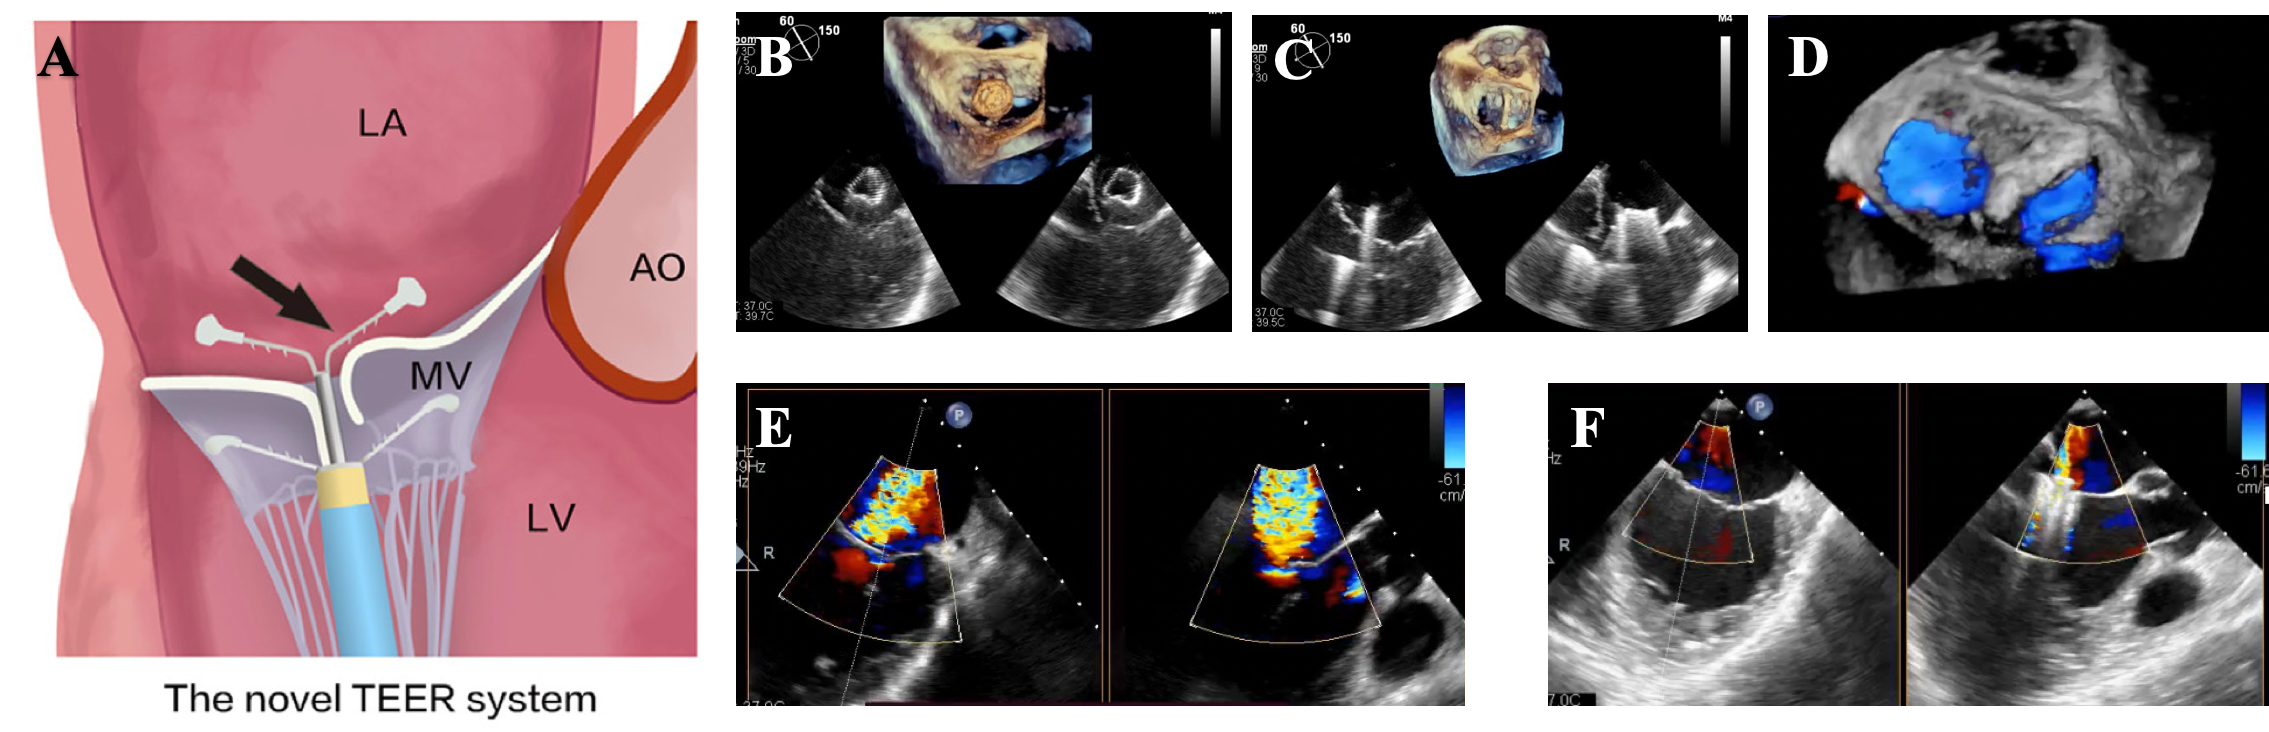

The ValveClamp system (Hanyu Medical Technology) is a newly developed transapical system that facilitates TEER through a simplified procedure and the use of wider clip arms (Supplemental Figure 1). Our team previously reported our preliminary single-center experience with the ValveClamp system in a series of SMR patients with short-term follow-up data.15 Here, we report the mid-term outcomes following TEER using the ValveClamp system from a multi-center database of patients with both aSMR and vSMR, and further evaluated the predictors of a residual MR of at least 2+.

We prospectively analyzed the clinical and echocardiographic data of a cohort of consecutive patients who were screened for severe SMR and indicated for TEER using the transapical ValveClamp system at 10 centers in China between March 2021 and May 2023. The main exclusion criteria were primary MR, severe mitral calcification, endocarditis, rheumatic mitral valve disease, a combination of other severe valvular heart diseases, or coronary stenosis requiring intervention. TEER using the ValveClamp system was performed under general anesthesia and transesophageal echocardiographic guidance, as previously described16,17(Videos 1-5).

SMR is a prevalent consequence of left atrial and left ventricular remodeling and is strongly correlated with adverse outcomes. Accompanied by major device and interventional revolutions, the use of TEER to reduce SMR has progressively matured into a safe and efficacious therapeutic option. The ValveClamp system is a recently developed TEER device composed of 2 matched, wide V-shaped clamping arms that are delivered straight up via transapical access using a sophisticated steerable delivery system under echocardiographic guidance.22

Previous studies have shown that TEER using the ValveClamp system for degenerative MR is effective, has a fast learning curve, and is associated with symptomatic improvement.16,23 Our previous case series15 was the first to report the feasibility of TEER for SMR with a small sample size. In the present study, the mean procedural and catheter time for ValveClamp implantation in 43 SMR patients was 57.05 minutes and 16.40 minutes, respectively, with more than 1 clip implanted in 18.60%(8/43) of the patients. This study demonstrated a much shorter operation time with a relatively lower rate of second clip implantation, regardless of MR etiology, compared with studies involving the MitraClip (Abbott) and Pascal (Edwards Lifesciences),24,25 indicating that the novel system could be easy to operate in both aSMR and vSMR cases. It is notable that all patients with SMR who successfully underwent TEER using the ValveClamp system reported an MR reduction of at least 1 grade before discharge, and 66.67%(26/39) had a residual MR of +1 or less, which is comparable to other TEER devices. The preliminary results indicate that the novel TEER device could also be efficacious in treating SMR because of its easy maneuverability and an acceptable safety profile.

Because the device is delivered to the left atrium through a 16-French straight introducer sheath, the apex can be closed with a regional purse-string suture. In our study, the preliminary results showed that the transapical ValveClamp transapical edge-to-edge mitral valve repair system could be safely performed with improved LVEF during follow-up, consistent with our previous study.29 Hence, the hemodynamic and clinical benefits support the notion that TEER using the ValveClamp system may be a good treatment option for high-risk SMR patients, irrespective of the etiology. However, further clinical studies are needed to investigate the long-term prognosis.